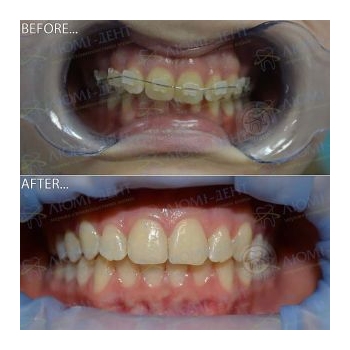

Выше можно увидеть фото до и после выравнивания неправильного прикуса у ортодонта пациентам «Люми-Дент».

Другие примеры работ наших докторов, исправление прикуса зубов в Киеве, фото до и после:

- На этой странице, и в разделах каждой отдельной услуги выравнивания зубов - можно увидеть много фото прикуса до и после лечения неправильного зубного смыкания у подростков, людей в возрасте. Фото до и после исправления прикуса в Киеве брекетами, пластинками, капами, трейнерами;